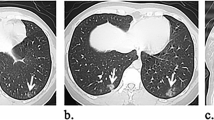

Among 269 patients for whom CT images obtained at the time of admission were available, the most frequent findings in severe cases were GGO, followed by bronchiectasis, air bronchogram, subpleural line, crazy paving pattern, consolidation, and bronchial wall thickening (Fig. 1). Abnormalities were distributed in the peripheral region, but in severe cases, they also spread to the central region, and in most cases, this was observed bilaterally (Fig. 2). While one case had pulmonary edema and another had aspiration pneumonia, all cases had lesions due to COVID-19 pneumonia; Fig. 3 shows two representative cases with such lesions on CT. In non-severe cases, GGO was observed in the peripheral region (Fig. 3a), but was also found in the central region in some patients (Fig. 3b). Elevated total scores were observed in severe cases (Fig. 4; see also Supplementary Table 1). Severe cases presented high scores in not only the lower lobes but also the upper lobes (Supplementary Table 1). The total score groups were associated with severe disease in a dose-dependent manner as shown by the increase in the crude ORs with increase in total score (Table 4, top). The OR adjusted for sex and age (aOR) showed similar results; adjusted for sex, age, and hospital size, the associations of the CT scores remained the same. In addition, when the total score was treated as a continuous rather than categorical variable, the OR increased by 1.5 (95% CI = 1.3–1.7) for every 1-point increase in total score, and increased by 1.4 (95% CI = 1.2–1.6) when adjusted for age, sex, and hospital size. In the ROC analysis of the total score, the AUC was 0.93 (95% CI = 0.89–0.98) and an optimal cut-off score of 11 was found to predict severe disease with 90.9% sensitivity and 82.2% specificity.

COVID-19 chest CT and X-ray images on admission. a Chest CT image of a 68-year-old male patient with ground-glass opacities (GGO) in the peripheral region (non-severe case). b Chest CT image of a 51-year-old male patient with GGO in the peripheral and central regions (non-severe case). c Anterior–posterior (AP) chest X-ray image of a 70-year-old female patient with cardiomegaly (severe case)

Among 168 cases for which chest X-ray images obtained at the time of admission were available, the common findings of severe cases included reticular-nodular opacities, cardiomegaly, and consolidation (Fig. 3c and Fig. 5). In particular, high CTR values were observed in both PA and AP views of severe cases (Fig. 6) and cardiomegaly was strongly associated with severe disease [OR = 52.1 (95% CI = 13.0–208.4); aOR for sex, age, hospital size, and patient positioning of chest X-ray = 24.6 (95% CI = 3.7–166.0)]. For cardiomegaly, a case was excluded from the calculation due to insufficient information to classify to PA or AP. Abnormalities were distributed in both lungs, in each zone, and showed a basal predominance (Fig. 7; see also Supplementary Table 2). High total scores were also observed in severe cases (Fig. 8; see also Supplementary Table 2). The total score groups were associated with severe disease in a dose-dependent manner (Table 4, bottom, crude OR), and the aOR controlling for sex and age showed similar results. In addition, adjusted for hospital size, the association remained similar between severe disease and chest X-ray score. When the total score was treated as a continuous rather than categorical variable, the OR increased by 1.2 (95% CI = 1.1–1.2) for every 1-point increase in total score, and the aOR increased by 1.1 (95% CI = 1.0–1.2), after adjustment for sex, age, and hospital size. An ROC analysis of the total score revealed that the AUC was 0.91 (95% CI = 0.86–0.97) and an optimal cut-off value of 9 predicted severe disease with 83.3% sensitivity and 84.7% specificity. Considering the presence of cardiomegaly on admission, for patients without cardiomegaly on admission, a high chest X-ray score of ≥ 9 showed a strong association with severe disease (crude OR = 44.1; 95% CI = 5.1–377.7; aOR controlling for sex, age, and hospital size = 11.7; 95% CI = 1.1–119.5). In patients with cardiomegaly on admission, a high chest X-ray score was not associated with severe disease (crude OR = 1.3; 95% CI = 0.1–20.7).